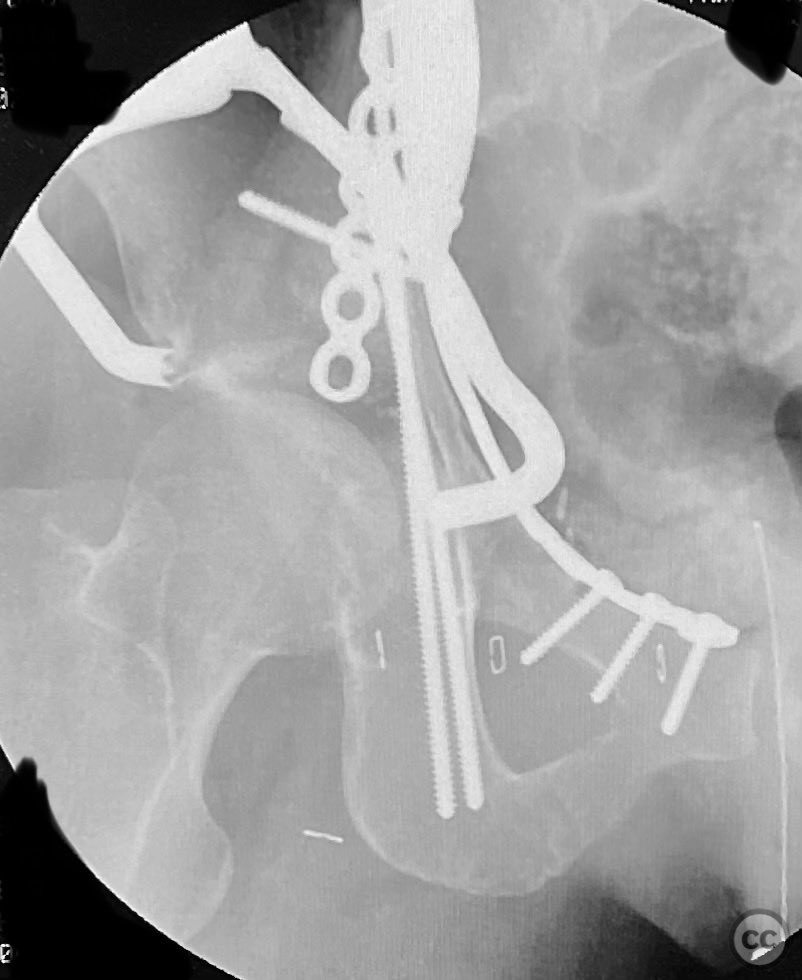

Anatomical surgical approach:  A classical ilioinguinal approach was performed, developing the lateral, middle, and medial windows. The intrapelvic interval was used to access the quadrilateral surface and posterior column. The rhomboid cortical fragment was excised to allow direct visualization and manipulation of the impacted posterior medial dome fragment. Reduction was achieved using a spiked pusher under fluoroscopic guidance. The defect was filled with morselized allograft, and the rhomboid fragment was anatomically reduced. The anterior column was stabilized with a contoured plate. Posterior column reduction was further improved using a reduction clamp applied with one tine lateral to the anterior inferior iliac spine (AIIS) and the other on the quadrilateral surface via the middle window, followed by lag screw fixation.

This case demonstrates that certain impacted dome fragments, which are otherwise inaccessible, can be directly addressed by temporarily removing overlying cortical fragments. The ilioinguinal approach, specifically through the middle window, provided unobstructed access for clamp placement and direct manipulation of both anterior and posterior column fragments. Sequential reduction and stabilization were facilitated by direct visualization and intraoperative fluoroscopy, allowing for anatomical restoration of the articular surface.

Orthopaedic implants used:   Contoured intrapelvic reconstruction plate, contoured anterior column plate, lag screws, morselized allograft